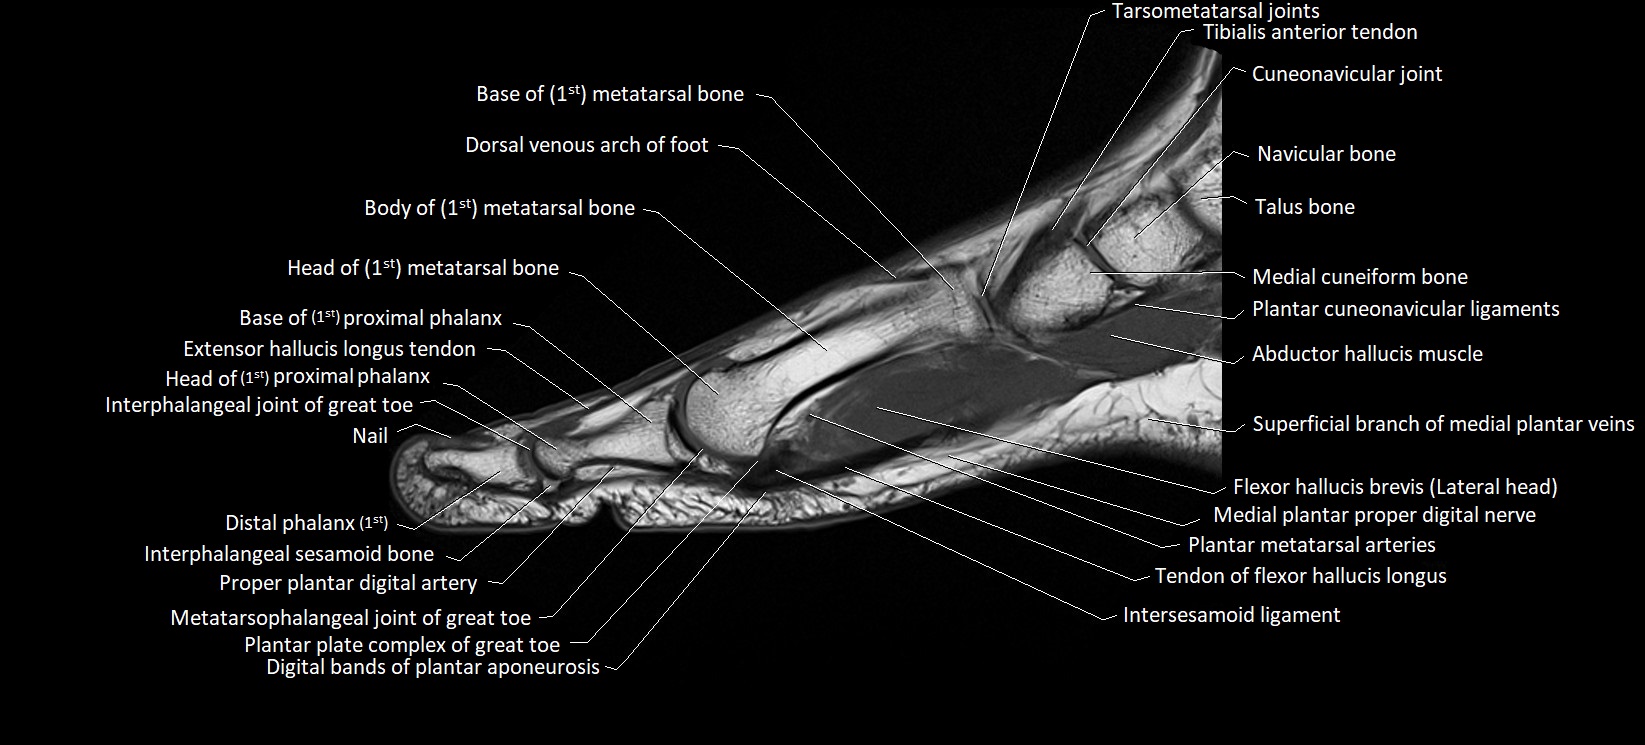

MRI image